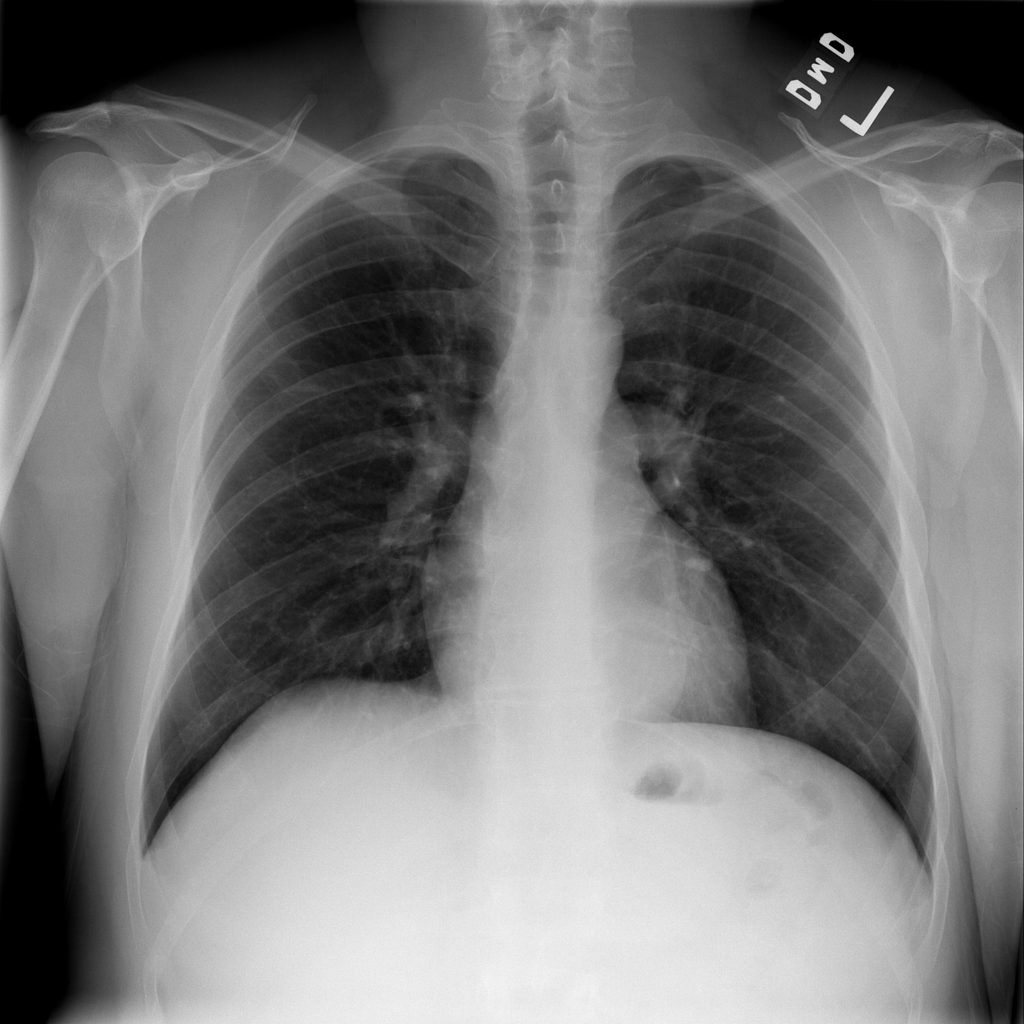

Showing up to 90 reference images for Hernia.

PAT-C048 · IMG-001Hernia

PAT-C048 · IMG-001

PA